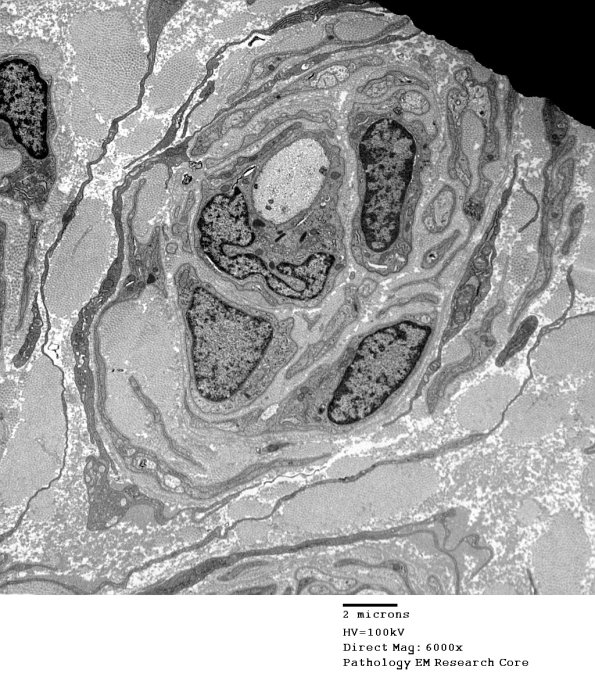

There are multiple well-formed onion bulbs surrounding thinly myelinated central axons. (electron micrographs)